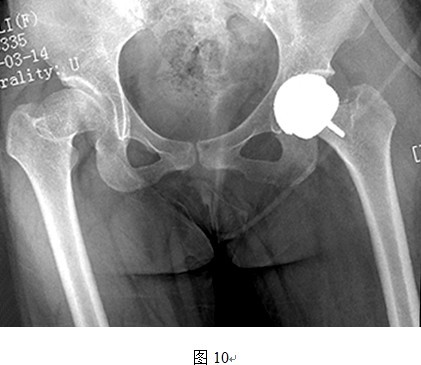

5. THRA不能有效延长肢体

THRA另外一个先天不足就是,从假体本身的设计来看,THRA假体本身不存在延长肢体长度的功能。普通THR的股骨侧假体可通过使用加长头、组配式股骨颈等设计来延长肢体长度,而THRA置换股骨头后,股骨头颈的长度没有明显变化。因此,只能从改变髋臼位置来使得股骨头中心下移,达到部分恢复肢体长度的目的。但是,对于DDH来讲,存在多个不利于肢体长度恢复的因素。首先,DDH假臼形成或者原始髋臼非常浅,加之表面置换不切除头颈情况下阻碍术者视野,想要定位真正的髋臼旋转中心有时比较困难,髋臼下移不一定能够完全实现;其次,即使找到并定位了真臼的旋转中心,但因软组织挛缩严重,术中股骨侧无法充分下移,可能出现无法复位的问题(图6);另外,还有一些患者患侧股骨颈本身就发育短缩或者存在髋内翻(颈干角变小),即使恢复了真臼的旋转中心,股骨侧也可以顺利复位,但是患侧肢体仍旧较对侧短缩(如图13所示左侧股骨颈短缩且内翻,采用THRA无法恢复肢体长度)。

原位表面置换对右侧VI度发育不良延长肢体毫无用处,因股骨头及粗隆部上移过多,右侧肢体短缩缩严重,可能需要转子下截骨才能复位关节,不适合行THRA手术。

图中所示左侧股骨颈短缩明显,进行THRA后因股骨颈长度不能延长,因此肢体长度不能得到恢复。